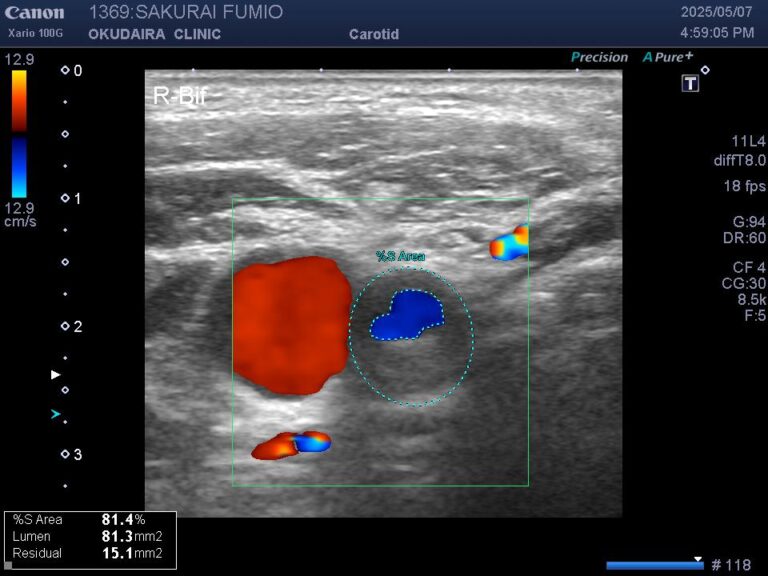

眼で見る動脈硬化